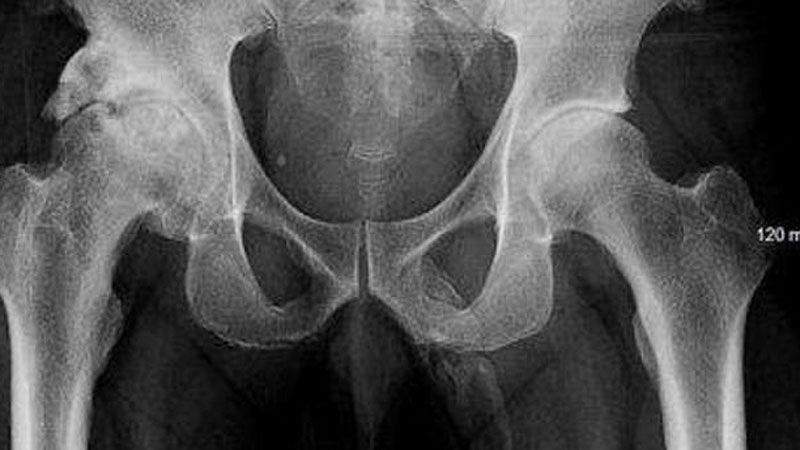

Mientras lo revisaban, los médicos le tomaron una radiografía de la pelvis para verificar que no había huesos rotos, pero encontraron algo más extraño de lo que esperaban.

Le dijeron al hombre que se estaban formando células óseas dentro de su pene, en ese momento se levantó y salió del hospital, ignorando el consejo de los médicos y nunca regresando.